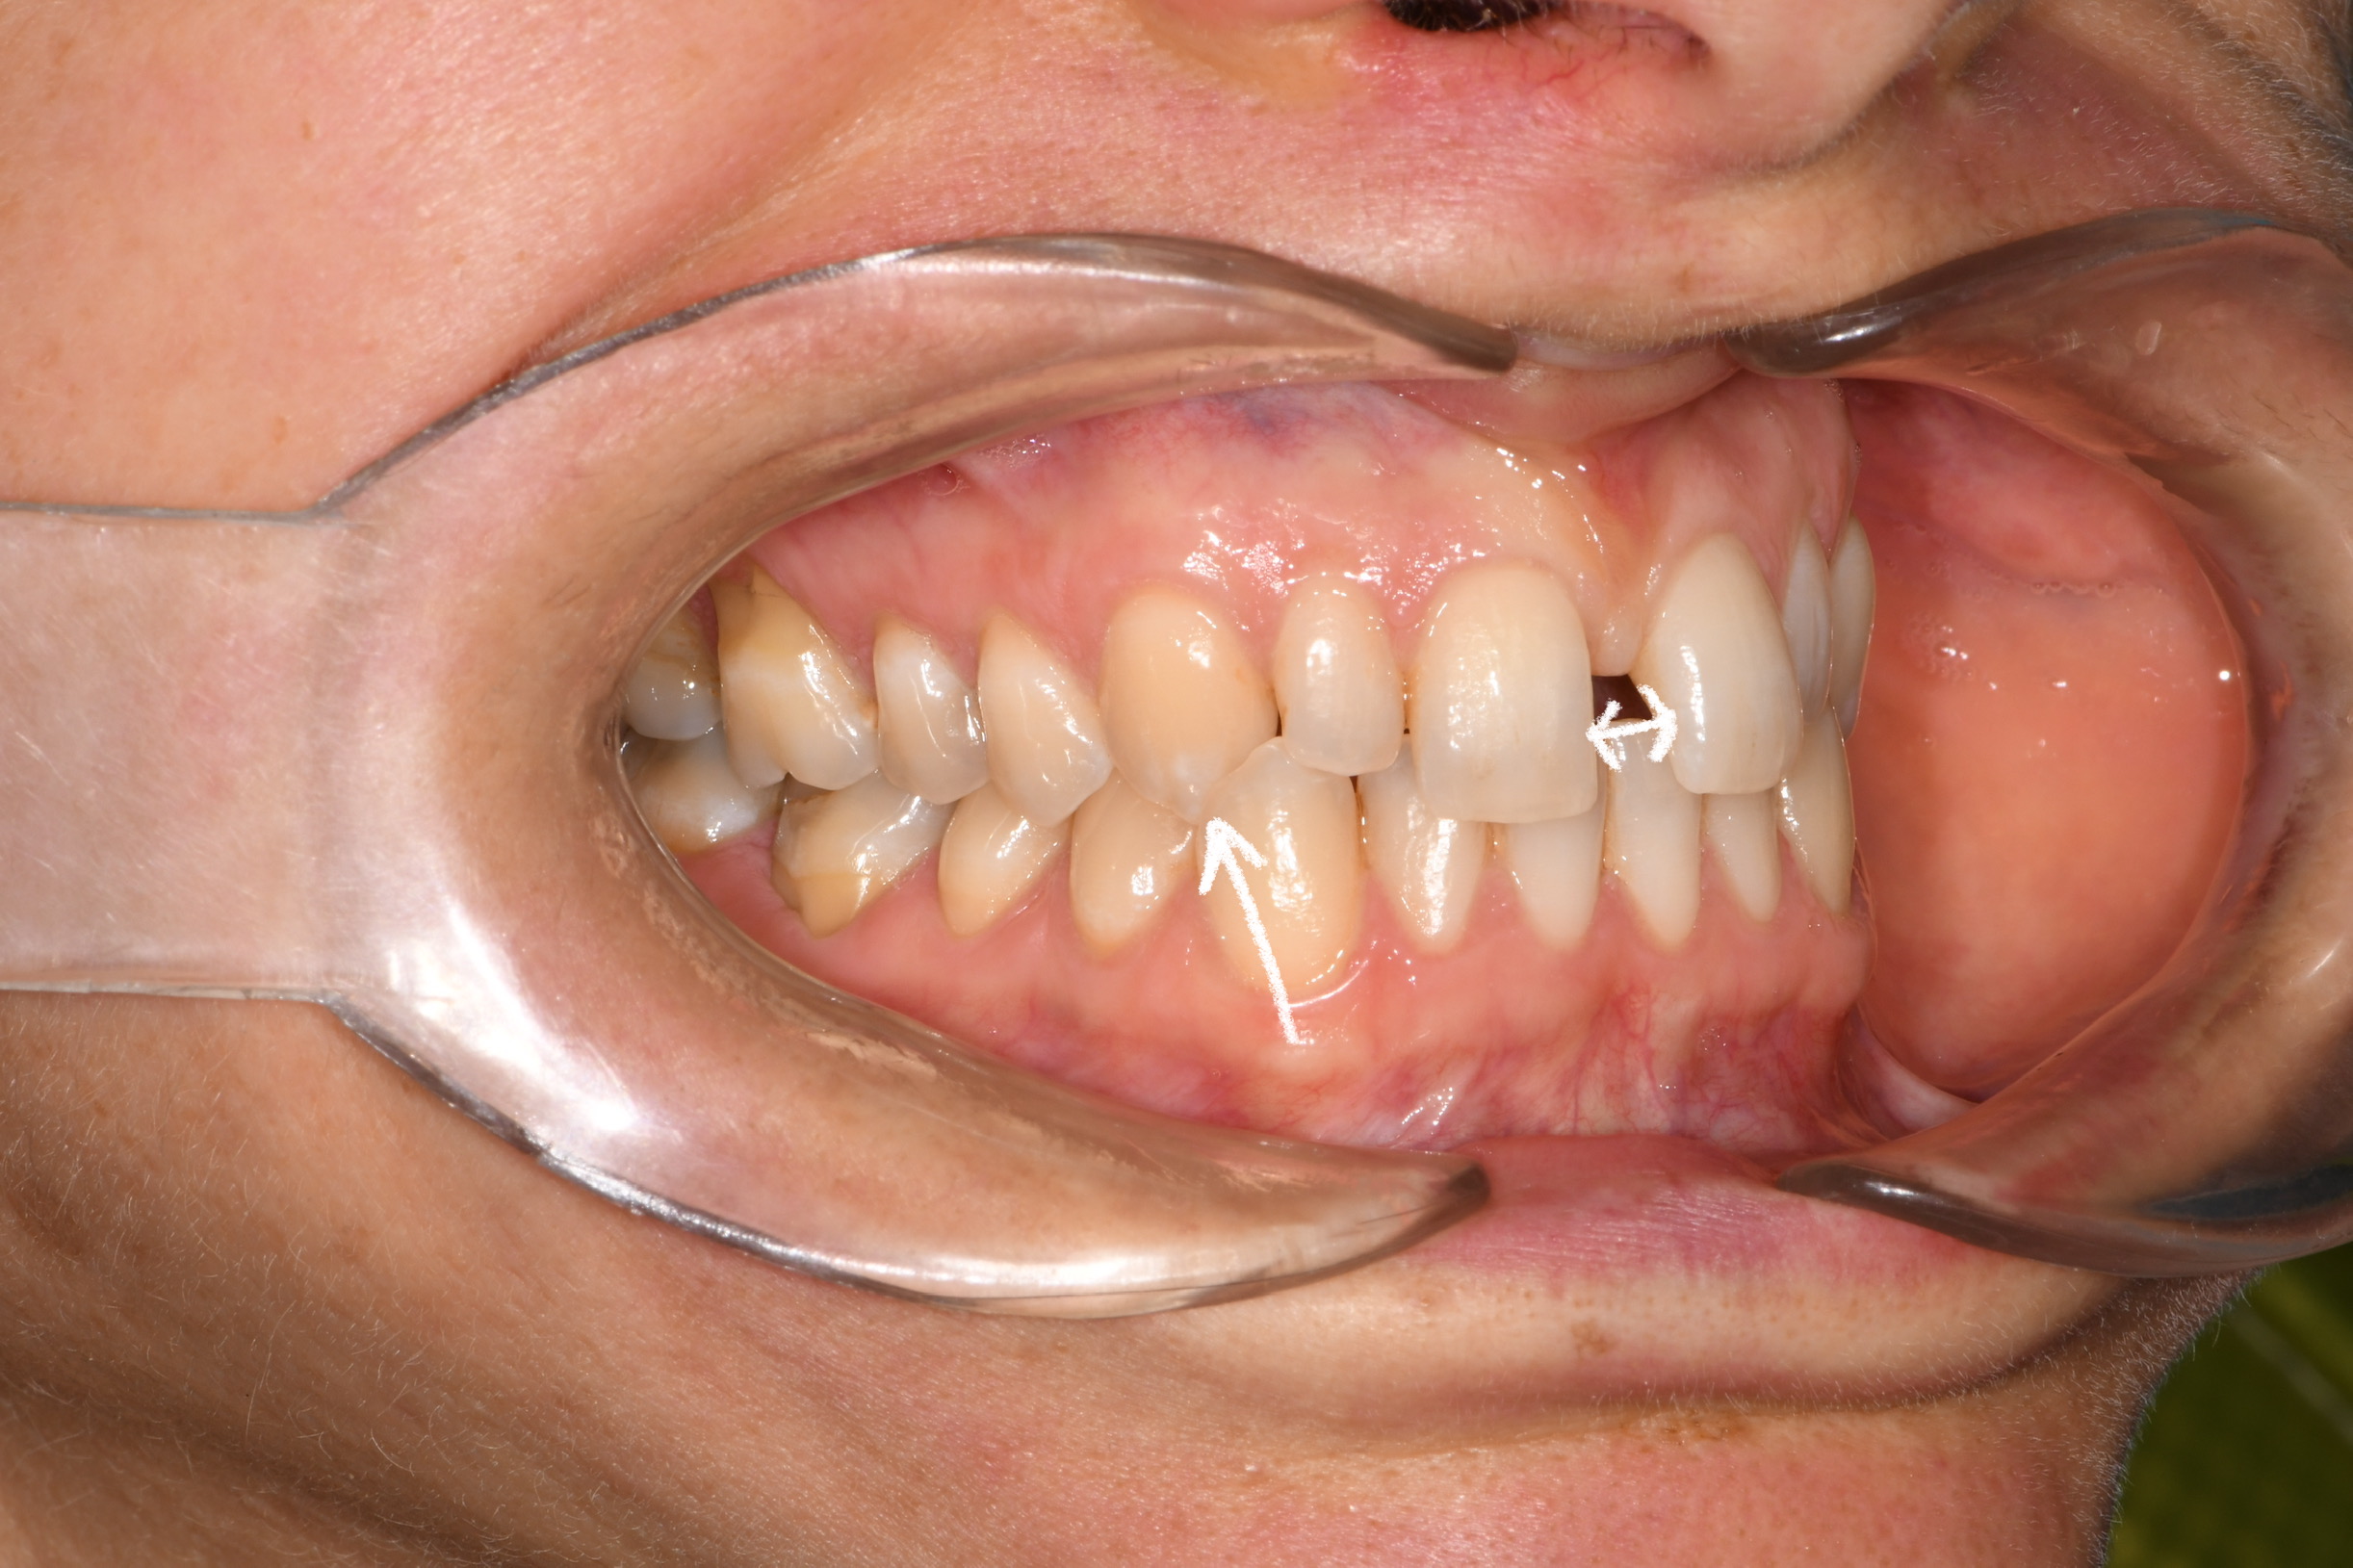

Az elmúlt évekből rengeteg szakmai referenciát tudnánk bemutatni, amelyek különböző fogszabályozási problémákat oldottak meg. Válogatva a több száz esetből, ezen az oldalon olyan képeket, információkat igyekeztünk bemutatni, amelyeknek a segítségével a jövőbeni pácienseinknek azt tudjuk üzenni: A Te fogsorod is lehet gyönyörű!

(Képeket a Pácienseink külön írásos beleegyezésével mutatjuk be!)